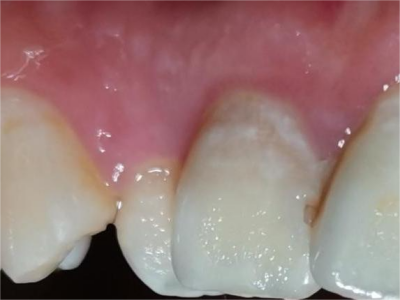

牙龈炎可先引起牙齿与牙龈之间的沟(龈沟)加深,然后牙龈充血,炎症围绕一个或多个牙齿,伴牙龈乳头肿胀和易出血。一般无痛,可自行消退,也可维持轻度炎症数年。

牙龈炎常见的病因是口腔卫生差,不良的口腔卫生使牙菌斑沉积于牙齿与牙龈之间,造成龈沟加深,另外牙结石、不良修复体等也可造成牙龈炎的发生。